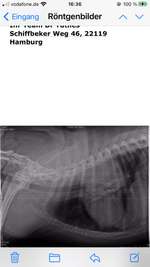

Mandelentzündung oder doch etwas anderes?

Meine 9 Monate alte fr.Bulldogge hat seit einer Woche Nasenlaufen, Probleme beim schlucken, erbrechen ( visköser schleim mit leicht blutiger Farbe ) und Abgeschlagenheit. Er nimmt nun seit 4 Tagen Antibiotika aber wir sehen keine Verbessrung. Er isst mittlerweile kaum bis nichts mehr, und ...